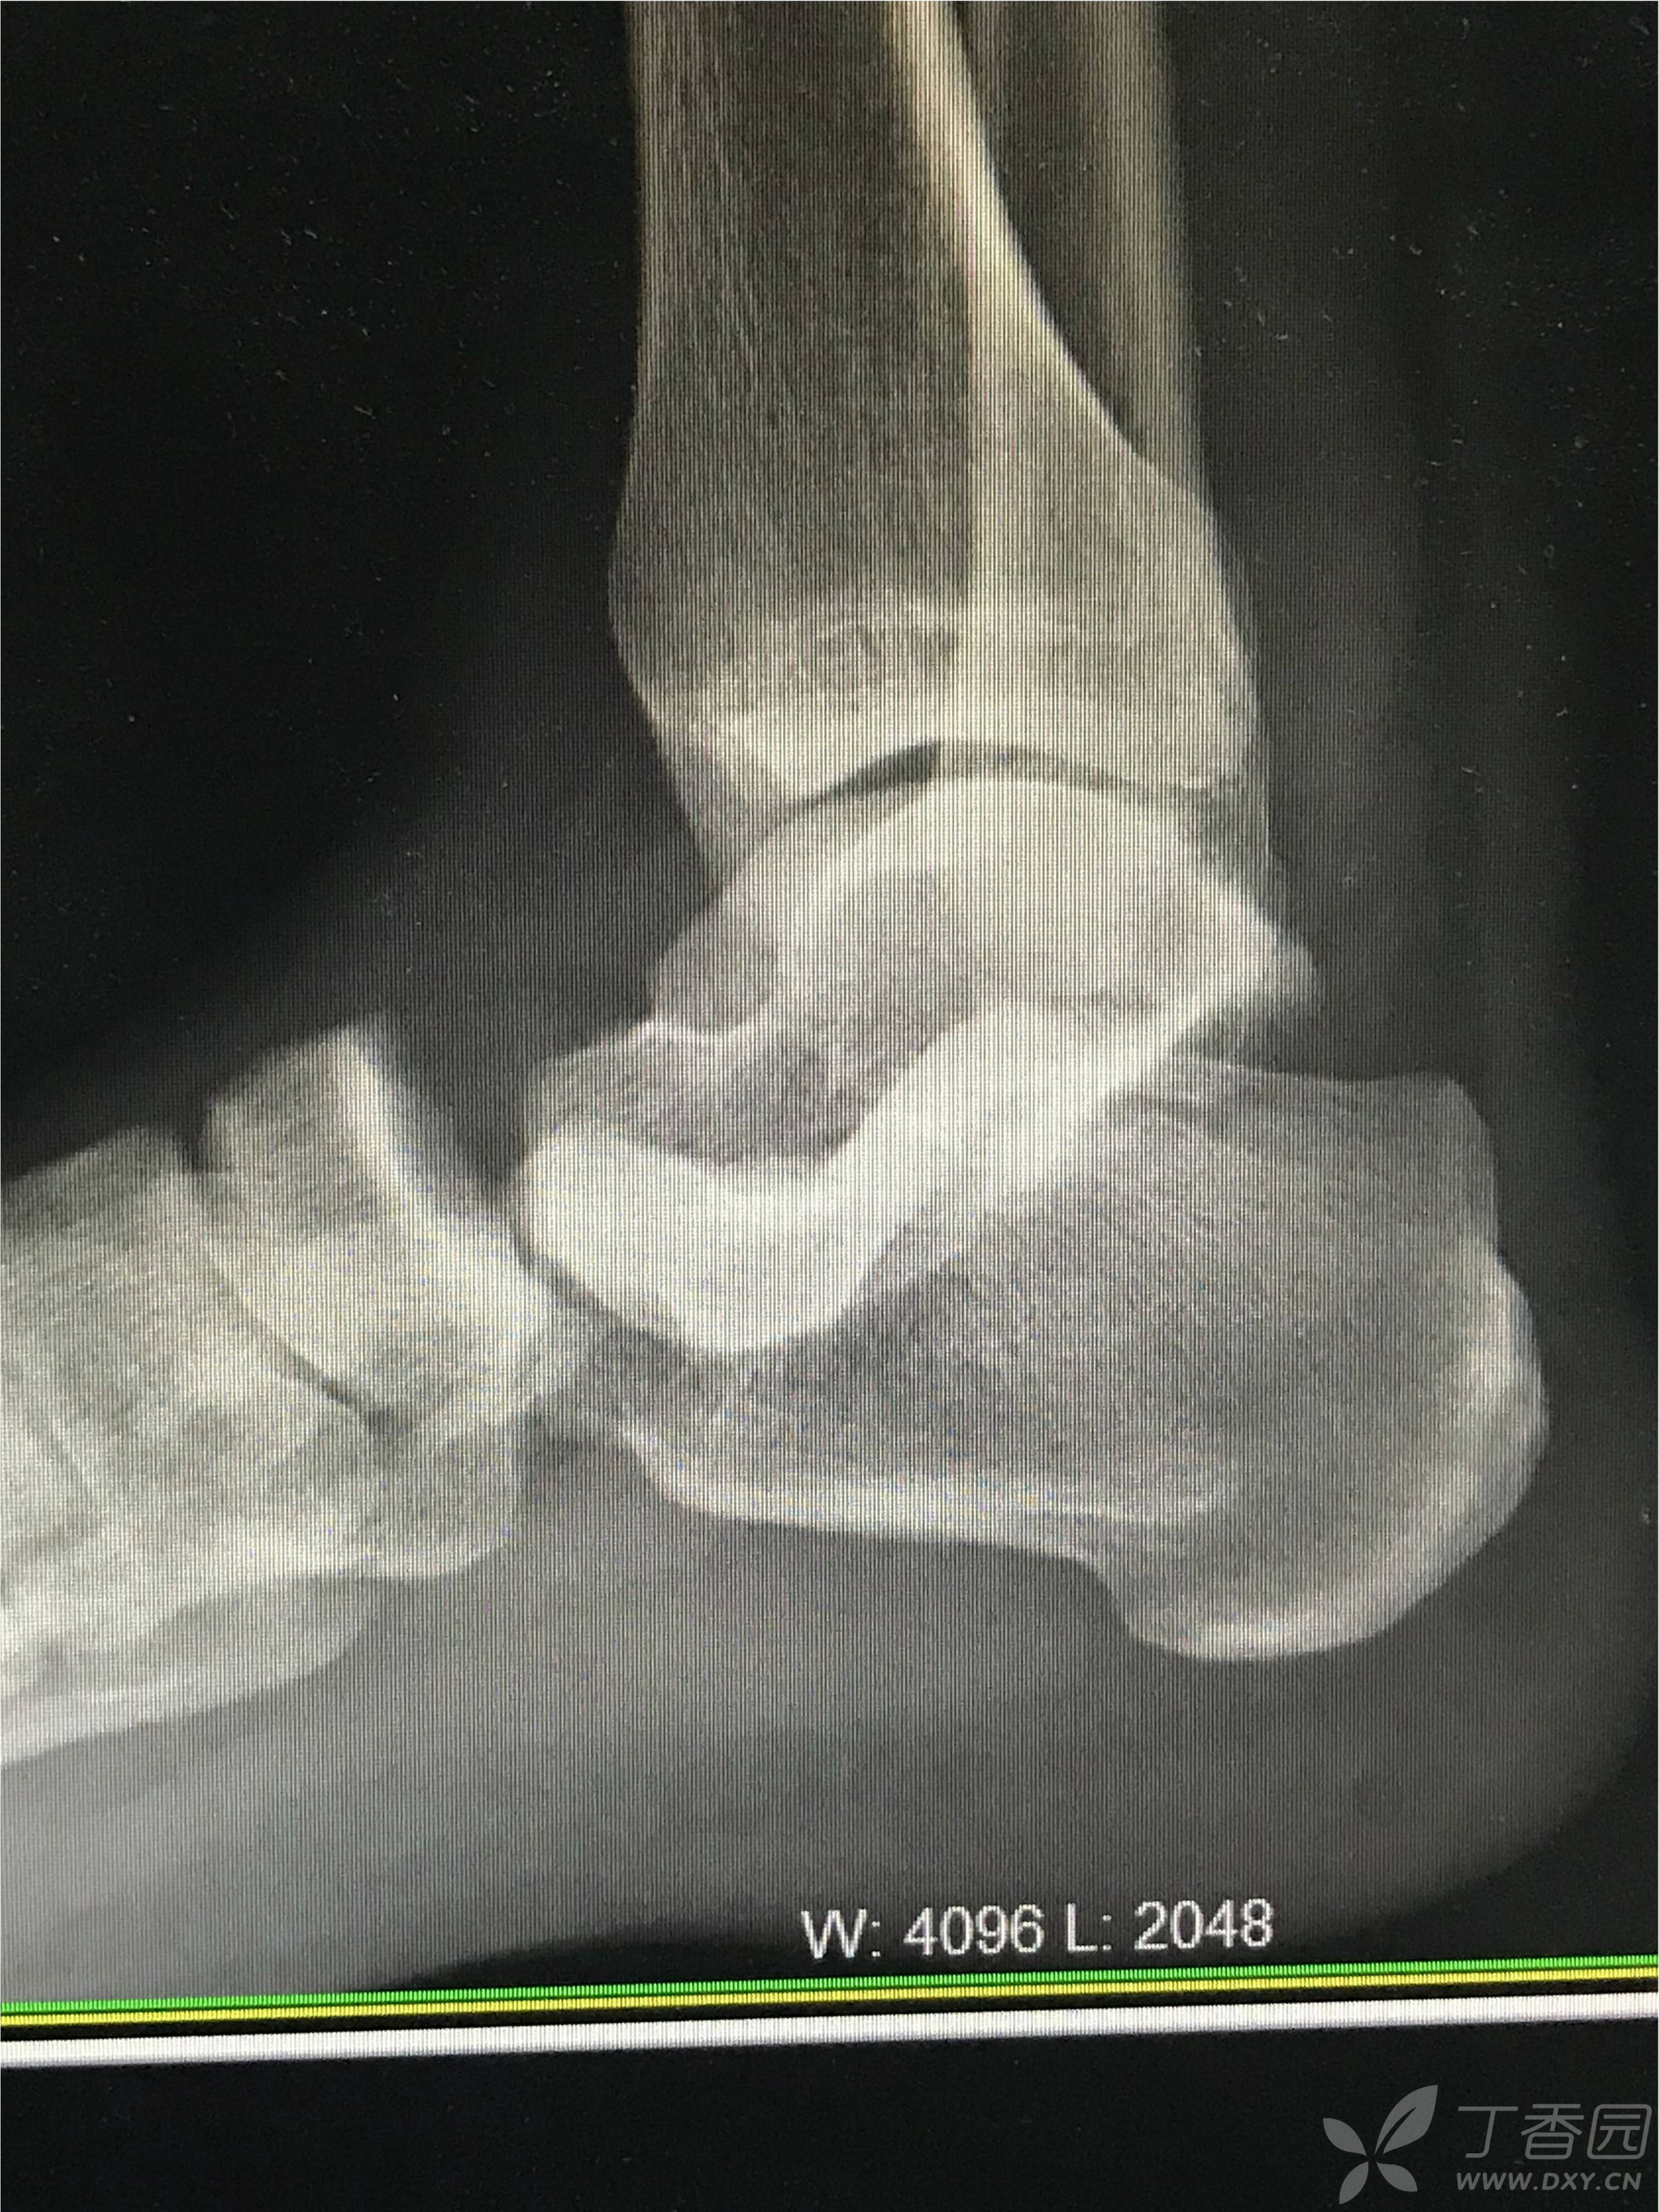

距下关节脱位合并距骨后突骨折病例帖

图片尺寸2976x3968